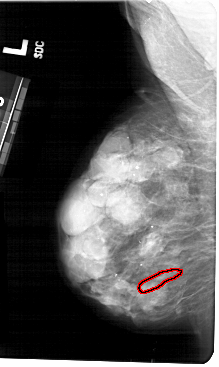

A_1484_1.LEFT_MLO

LEFT_MLO LINES 5491 PIXELS_PER_LINE 3271 BITS_PER_PIXEL 12 RESOLUTION 43.5 OVERLAY

FILE: A_1484_1.LEFT_MLO.OVERLAY

TOTAL_ABNORMALITIES 1

ABNORMALITY 1

LESION_TYPE CALCIFICATION TYPE PLEOMORPHIC DISTRIBUTION LINEAR

ASSESSMENT 4

SUBTLETY 1

PATHOLOGY BENIGN

TOTAL_OUTLINES 1

BOUNDARY